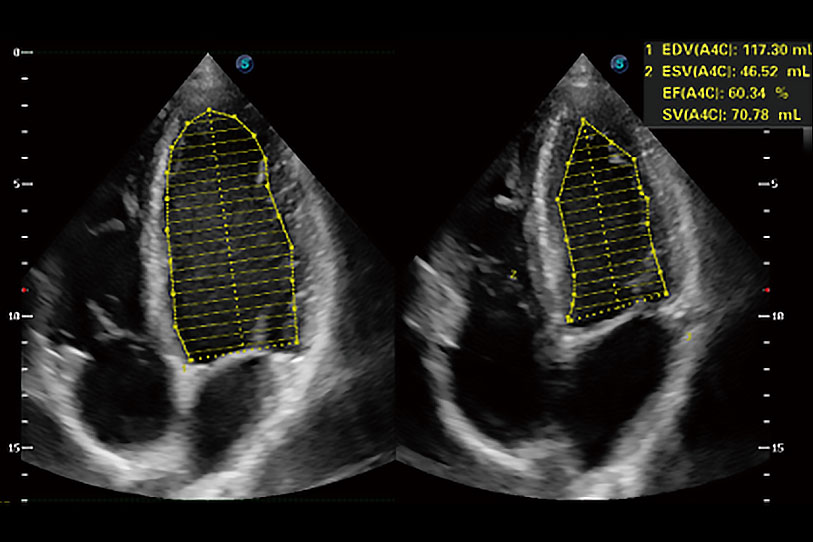

能夠基于左心室壁追蹤和辛普森法,自動計算射血分數(shù),支持多個可移動點描跡,與手動測量相比,極大節(jié)省了動物醫(yī)生的時間和精力。